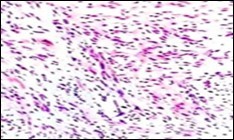

Figure 6.Soft tissue perineurioma with foci of spindle cells with wavy nuclei and an admixture of myxoid and collagenous stroma 15.